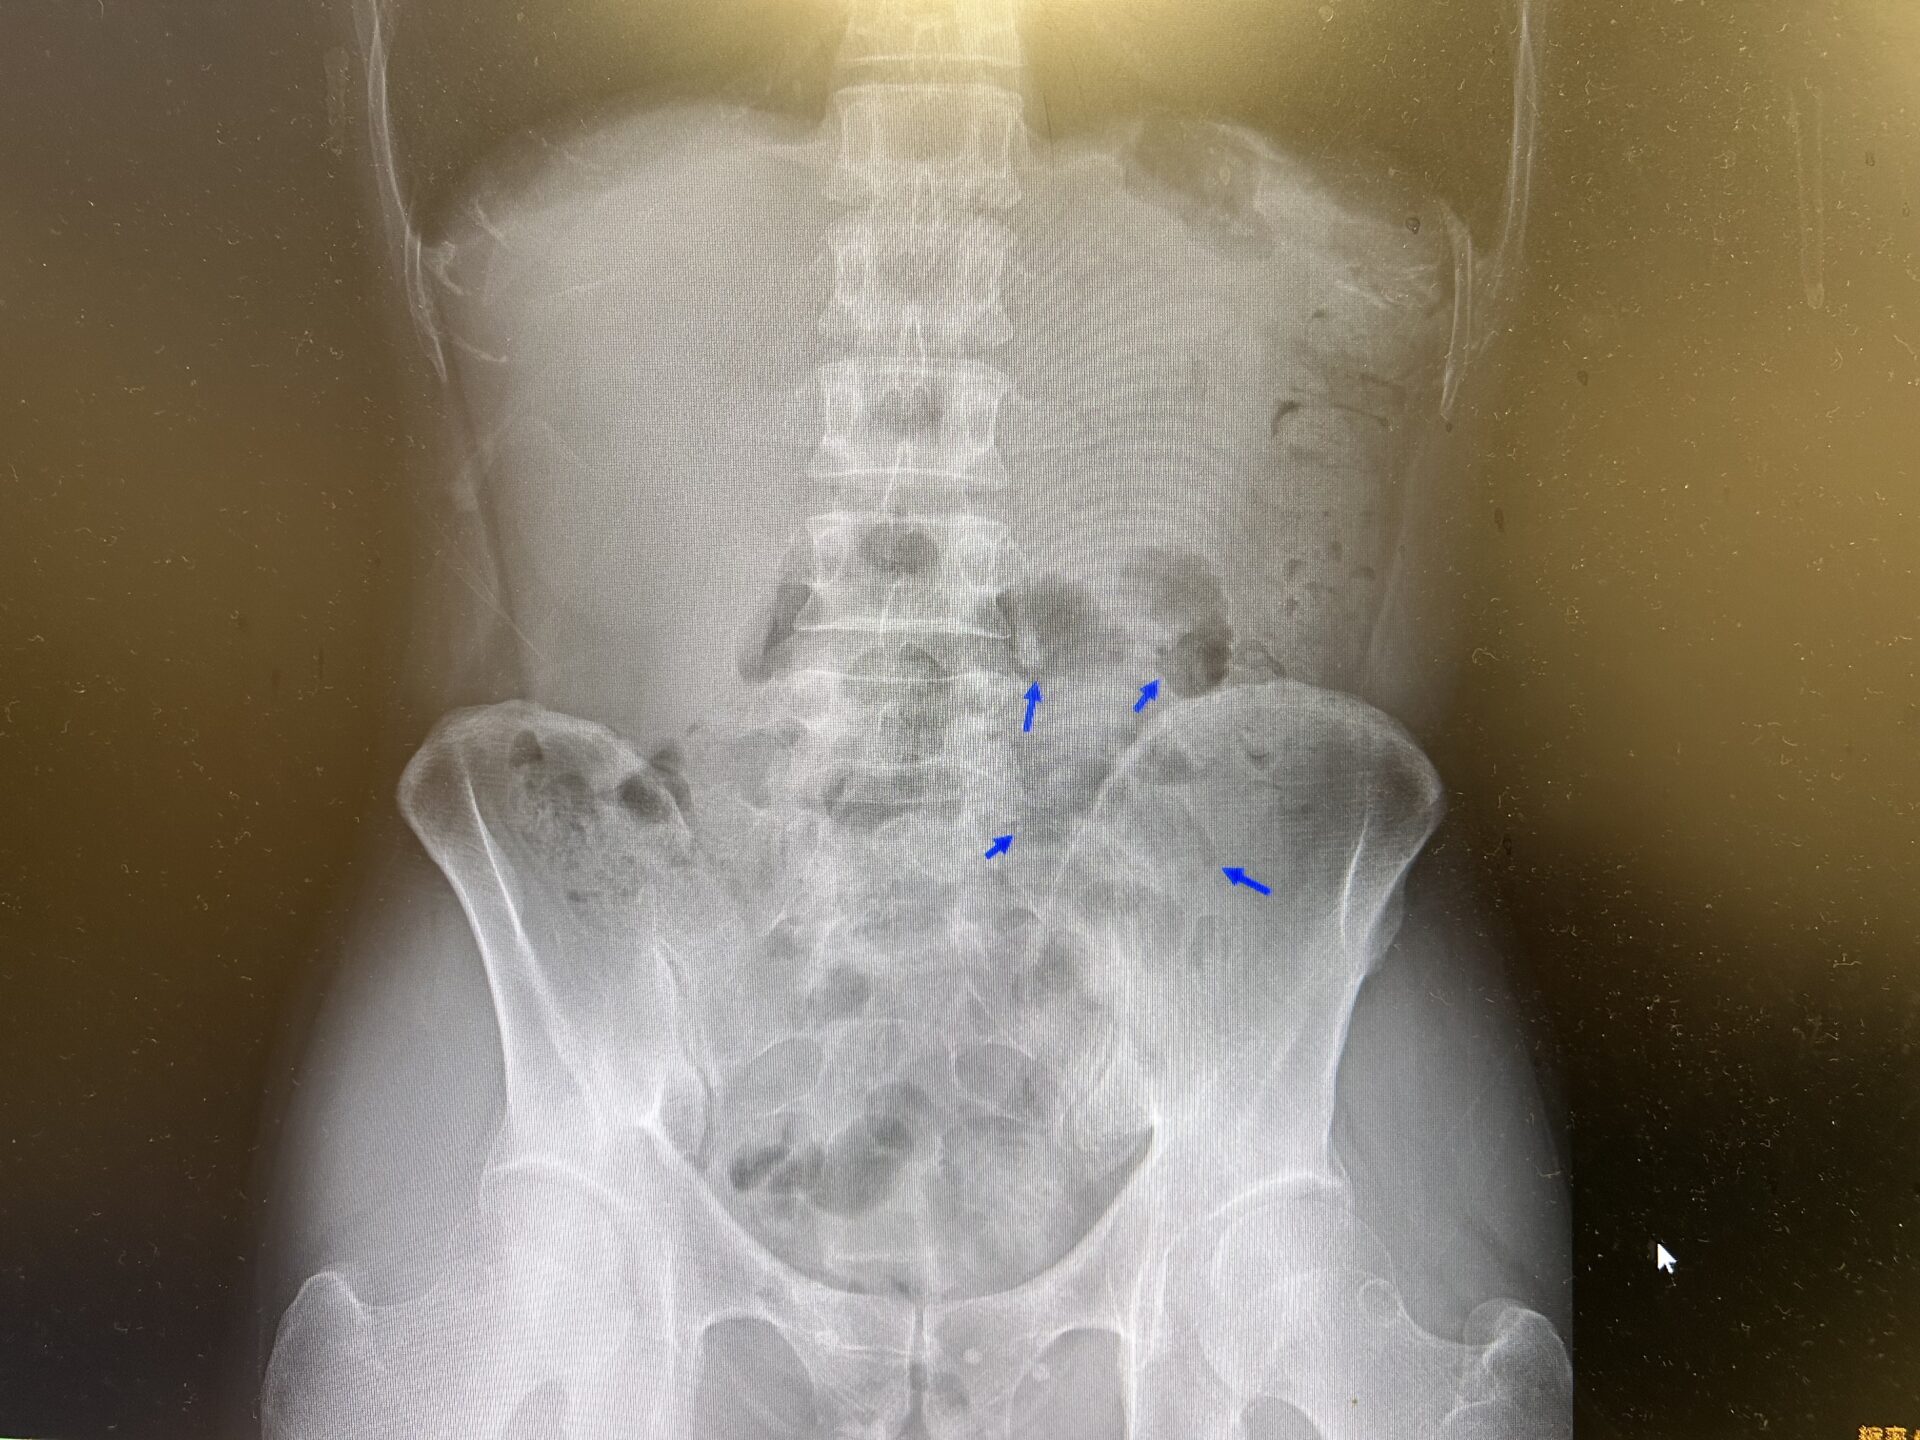

すると、緊急採血の結果はWBC9080↑(正常値300-9000)CRP1.40↑(正常値<0.3)と軽度炎症反応の上昇あり。また、レントゲン上では二ボー像は無かったものの、小腸ガスがところどころに認められており、腸蠕動が鈍くなるサインが出ていました。

【立位腹部x-p:小腸ガスがところどころに認められています】